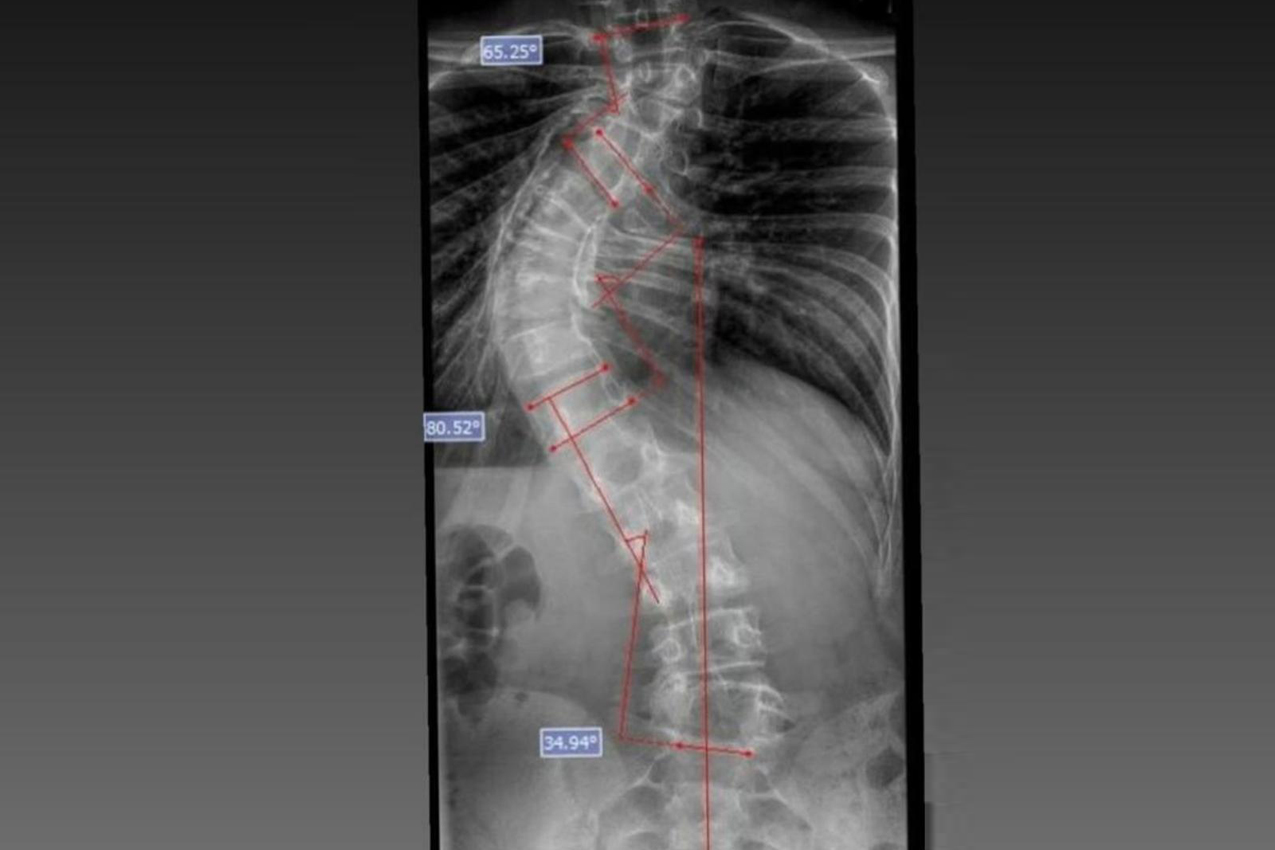

Laura era portadora de escoliose e, em agosto de 2025, realizou a cirurgia de correção da coluna, o que lhe permitirá ter uma vida normal de agora em diante. Moradora de Bom Sucesso do Sul, região Oeste do Paraná, é acostumada a andar a cavalo, mas com o problema na coluna a prática estava longe de ser prazerosa.

DIAGNÓSTICO - A escoliose pode ter diferentes causas, sendo classificada em idiopática (sem causa definida), sindrômica (associadas a síndromes genéticas), neuromuscular (decorrente de doenças como paralisia cerebral e atrofia muscular espinhal) e congênita (presente desde o nascimento). Em todos os casos, o diagnóstico precoce e o acompanhamento especializado são fundamentais para determinar a melhor abordagem terapêutica.

O médico João Elias explica que a escoliose é um termo usado para quando você olha a coluna e percebe uma curvatura. Pode acontecer por várias causas, desde uma escoliose congênita, quando o bebê nasce com uma vértebra mal formada e essa vértebra vai levando ao desenvolvimento de uma deformidade na coluna; a neuromuscular, causadas por doenças neurológicas ou musculares, como uma paralisia cerebral, até as idiopáticas, causadas por alterações genéticas e que podem se desenvolver apenas na adolescência.

Segundo ele, o verão é o período em que mais se diagnostica a doença. Por causa do uso de roupas mais leves, é mais fácil notar a alteração na coluna. Caso seja percebida alguma alteração, uma avaliação ortopédica deve ser marcada. “O diagnóstico precoce é importante. Quando a gente percebe que a coluna está iniciando uma curvatura é possível controlar essa curva. Fazer o procedimento com uma curvatura menor permite melhores resultados na cirurgia”, explicou.